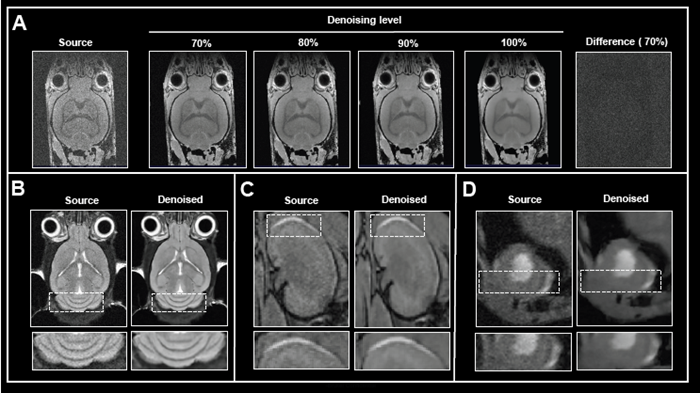

In addition to network options, the denoising level can be selected. Fig 2A shows the effect of applying various levels of denoising to image reconstruction.

Mouse brain data was obtained ex vivo, and the original data was rebuilt without and with increasing denoising levels (70-100%). Increasing the level of denoising produces images with gradually less noise. Importantly, no artifacts were introduced during the procedure.

Computing the difference images between the source and 70% denoised images revealed that only noise was selectively eliminated. If the original signal at the image's edges is reduced due to bandwidth selection, high denoising levels (90 and 100%) can result in a hazy look of edges.

The appropriate denoising level, which balances efficient noise removal with edge blurring, must be determined for each data set or, at the very least, each application protocol.

Figure 2. The effect of image denoising on image quality. A) Applying increasing levels of denoising. Shown are axial images of a 3D T1-weighted FLASH ex vivo data of a fixed mouse head acquired at 9.4 Tesla without (Source) and different levels (70-100 %) of denoising. A difference image between the source and 70 % denoised images was computed. B)-D) Comparison of in vivo images reconstructed with no denoising and with 70 % denoising. B) Coronal T2-weighted TurboRARE images of a mouse brain acquired at 3 Tesla. C) Coronal 3D FISP images of mouse kidney acquired at 7 Tesla. D) Short axis view of a mouse heart acquired with a flow-compensated triggered FLASH sequence at 9.4 Tesla. For different data, either no denoising (Source) or denoising using individual networks and a pre-denoising of 50 % was applied (Denoised). Image Credit: Bruker BioSpin Group

The efficacy of Smart Noise Reduction was illustrated using in vivo mouse data from various organs collected at various magnetic field strengths (Fig 2B-D).

Compared to reference images of the brain, kidney, and heart, reconstruction with 70% denoising resulted in images with substantially less noise and a better look of anatomical details and edges.